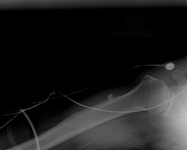

Visão lateral de radiografia de luxação posterolateral do cotovelo

Acervo pessoal do Dr. Paul Novakovich